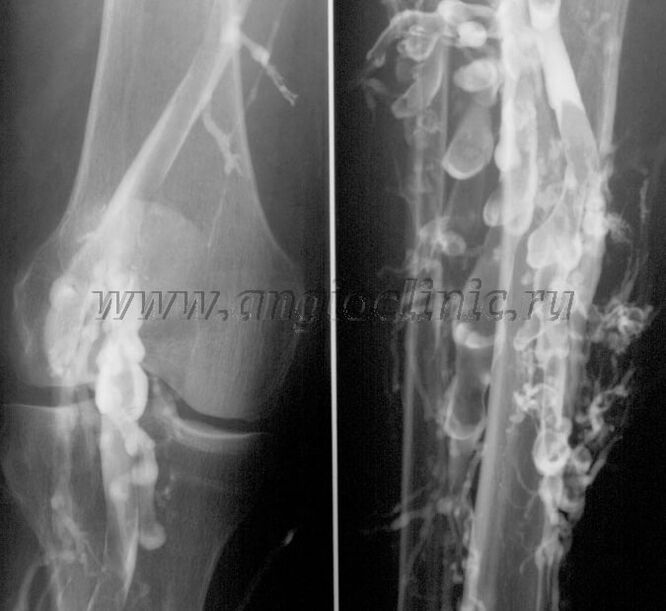

Velografi kontras

Biasanya, pemeriksaan ultrasound adalah mencukupi untuk diagnosis lengkap patologi vena. Walau bagaimanapun, dalam beberapa kes adalah perlu untuk mengkaji hubungan antara keadaan sistem vena dalam dan dangkal, terutamanya dalam kes kambuhan vena varikos dan vena varikos sekunder.

Untuk menyelesaikan masalah ini, pemeriksaan X-ray kontras digunakan. Urat saphenous ditebuk dan medium kontras diberikan. Pergerakan medium kontras diperhatikan pada monitor mesin X-ray dan semua ujian dan unjuran yang diperlukan dijalankan. Venografi pada masa ini hanya digunakan sangat jarang untuk vena varikos.